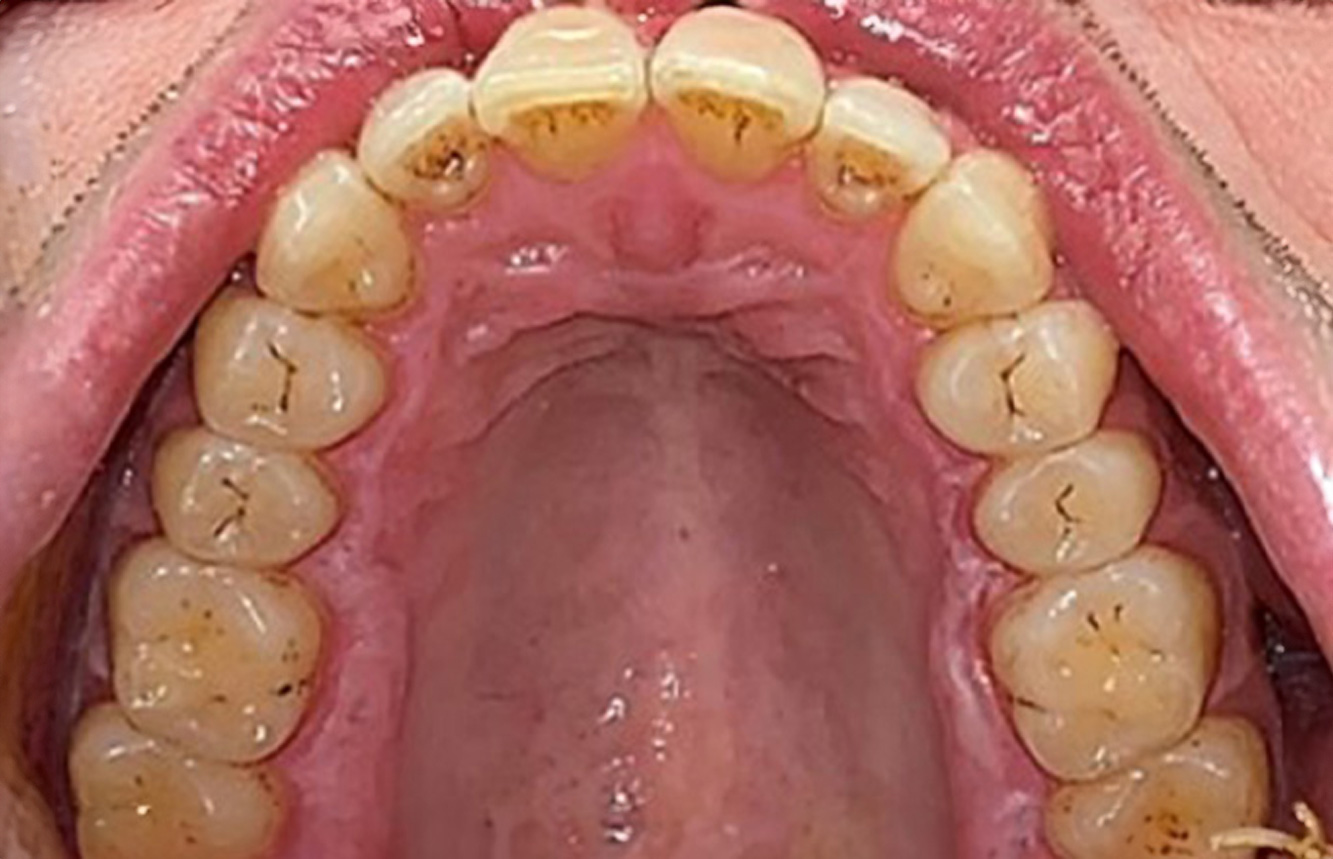

The healthy patient with pre-existing periodontal disease & peri-implantitis

The 28-Year-Old Cigarette Smoker with Dental Erosions

28-year-old patient, smoker, with erosions. The bidirectional relationship between oral and general medical health is very well known. It is no longer sufficient – and arguably even old-fashioned – to consider intraoral conditions in isolation. In order to create a personalized, case-specific preventive and patient profile, it is essential to take a detailed medical history and perform diligent examination of the general medical and intraoral health, as well as considering the two in combination. more